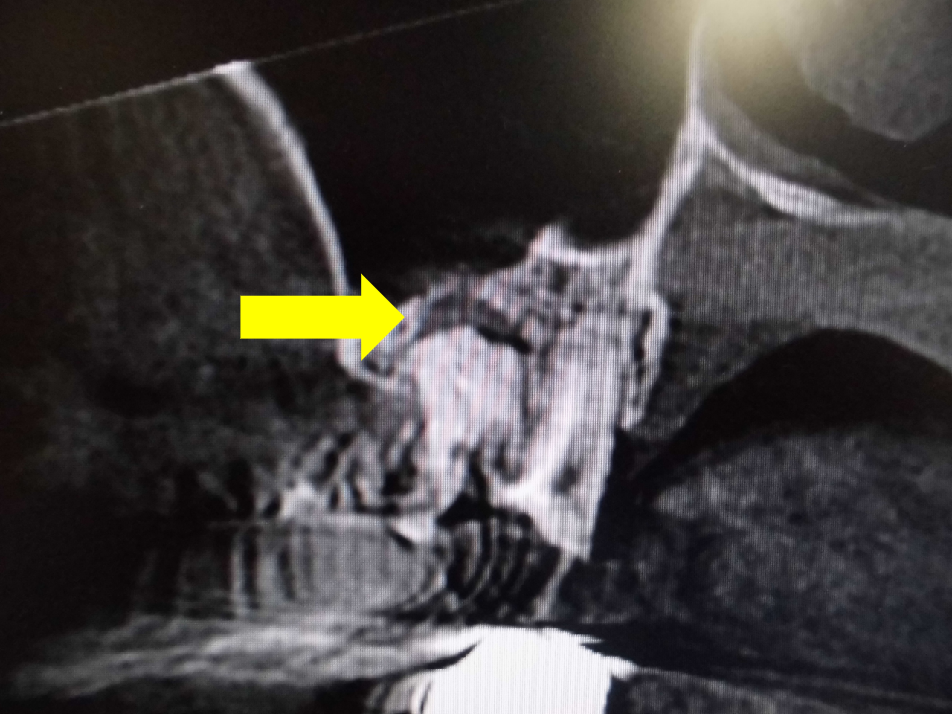

上顎洞との位置関係が確認できます。

CTでは近心の第二根管も確認できます。

原因が頬側近心根とわかりました。上顎洞粘膜が肥厚しているのもわかります。